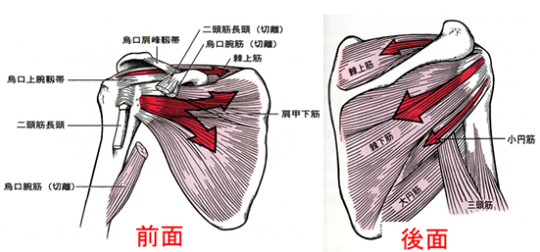

僧帽筋上部、三角筋、肩甲挙筋、小菱形筋、棘上筋、棘下筋、烏口腕筋、上腕二頭筋長頭・短頭、肩甲下筋、前鋸筋

の圧痛が徐々に緩和。

肩関節外転で三角筋、上腕二頭筋長頭・短頭、烏口腕筋

が特に運動痛著明。

腕を横に挙げていき、60度を過ぎると、肩甲骨が動いて行かないと腕は挙がりません。僧帽筋の深層にある肩甲挙筋の収縮と菱形筋の伸展(柔軟性)が欠かせません。しかし、それだけではなく、動き初めには棘上筋がまず動きますが、小さな筋肉で血流が停滞して炎症が出やすい筋肉です。

さらに、大胸筋、小胸筋、上腕二頭筋、烏口腕筋が短縮しやすく、疲れ、痛みが出やすい筋です。

大学3年生アーチェリー選手、2017年3月から弓を肩の高さに引き上げて保持できなくなる。腫れ、熱は無いが腕を横から挙げていくと60度蚊ら90度で痛みが生じ、120度以上は力が入らず180度腕が挙がらない。

棘上筋への置鍼(寸3、2番)、その後筋膜リリース3分間。施術時間7分間ほど。